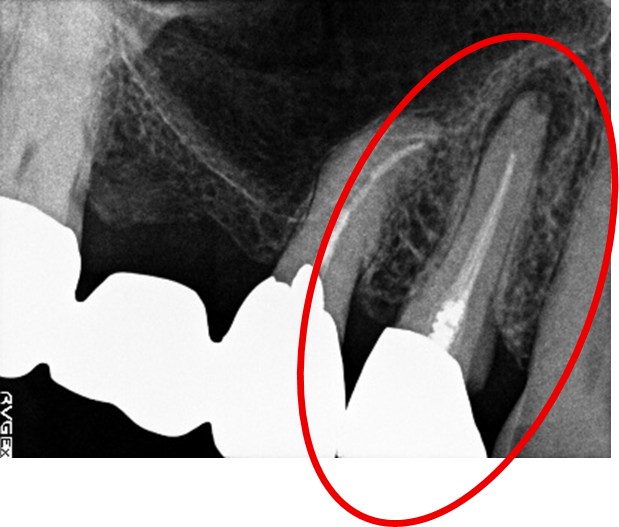

女性 Hさん 60代 (オールセラミック冠・インプラント)

主訴

右下のブリッジがゆらゆら動く。

治療内容

ブリッジの支台になっている奥の歯が、被せ物の中で虫歯になり、支台の役割を果たさず、前方の歯のみで支えられていました。前方の歯をそのままにして、後方の部分を切り離すと、そのまま取れてきました。中は、虫歯で歯根しか残っていない状況でした。この歯は、根管治療後、単独でオールセラミック冠を被せ、歯のないところにインプラントを埋入しました。

所感

今回の治療法には、次の3つの方法があります。

(1)虫歯になっていた歯の根管治療をし、土台を入れ、また再びブリッジにする。しかし、虫歯になっていたほうの歯は、ブリッジの支台として使うには、心もとなく長持ちしない可能性が高く、今度問題が生じたときには抜歯になる。

(2)虫歯になっていた歯に、単独で被せ物をし、歯のないところに1本だけの部分入れ歯を入れる。取り外しの入れ歯なので、自分の歯のような感覚で噛むことはできない。この方法も歯のない部分の負担を欠損の両側の歯に負担してもらうため、長持ちしない可能性が高い。

(3)虫歯になっていた歯に、単独で被せ物をし、歯のないところにインプラントを埋入する。欠損している部分の負担を前後の歯に負担させないので、歯を守ることができる。また、自分の歯と同じ感覚で食事をすることができる。

患者さんは、3つ目の方法を選択されました。一番長持ちし、これ以上歯を失わないためには、最良の方法だと考えます。

オールセラミック冠(失活歯):¥104,500(税込)

インプラント:¥363,000(税込)

合計:¥467,500(税込)

Before

冠の中で大きな虫歯になり支台の役割を果たしていませんでした。

【インプラント埋入前】

冠はブリッジを切断しただけで取れてきました。軟化象牙質を取り除いたところ、歯根しか残っていない状況で保存できるかどうかのぎりぎりのところでした。

After